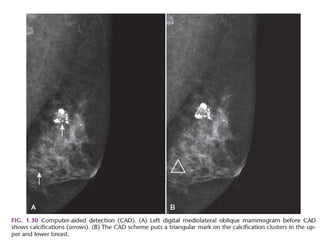

. • CAD with alarge area of type 3 enhancement CAD Computer Aided Detection is a purely kinetic evaluation. It does not evaluate the anatomy or pathology of the images. CAD looks at the curves and peak enhancements for the contrast (automated kinetics). It can do multiplanar reconstruction and subtraction very well and very quickly – it also has a good measurement package. The CAD shows a large area of red superimposed on the breast lesion in the image on the left. It also has some very nice features, including motion registration during subtraction, which can correct for a patient's movement during the exam - something not all MRI scanners can do. In CAD, red is bad: it means type 3 washout, and probably cancer.